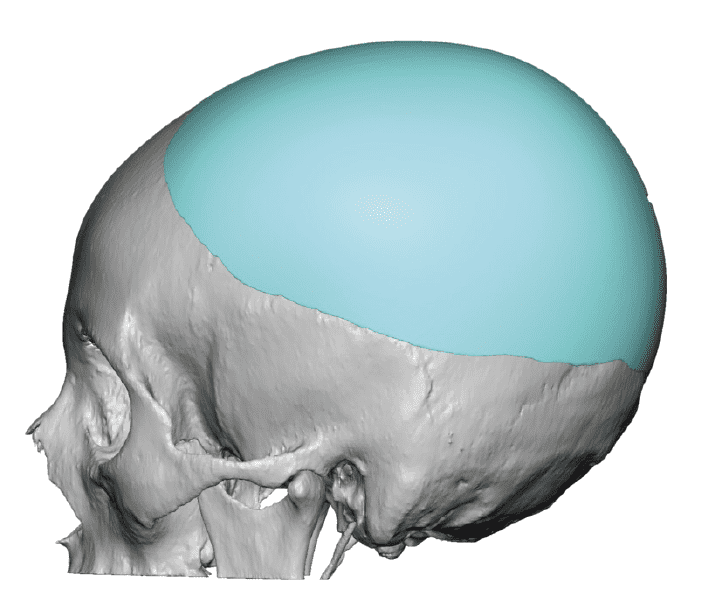

Patient 28

Desire for rounder shape to the top of the head from a congenital parasagittal deficiency skull shape.

Custom skull implant designed to fill in the parasagittal deficiencies.

Desire for rounder shape to the top of the head from a congenital parasagittal deficiency skull shape.

Custom skull implant designed to fill in the parasagittal deficiencies.